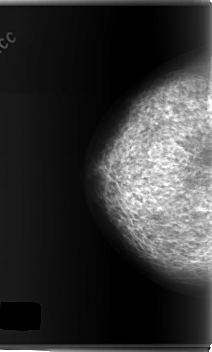

C_0148_1.RIGHT_CC

C_0148_1.LEFT_CC

LEFT_CC LINES 6008 PIXELS_PER_LINE 3592 BITS_PER_PIXEL 12 RESOLUTION 50 OVERLAY

FILE: C_0148_1.LEFT_CC.OVERLAY

TOTAL_ABNORMALITIES 1

ABNORMALITY 1

LESION_TYPE MASS SHAPE ARCHITECTURAL_DISTORTION MARGINS ILL_DEFINED

ASSESSMENT 4

SUBTLETY 2

PATHOLOGY MALIGNANT

TOTAL_OUTLINES 1

BOUNDARY